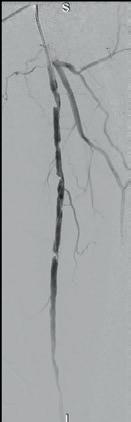

Arteriogram, left lower extremity

An arteriogram of the left lower extremity was performed via antegrade left common femoral artery access based on preoperative review of the lower extremity arteriogram from Uzbekistan. Scattered non-calcified plaque with moderate to high-grade stenoses were identified in the proximal and mid superficial femoral artery. Diffuse severe calcified tibial artery disease was identified. There was a long segment stenosis of the proximal and mid posterior tibial artery coupled with a more distal occlusion. The proximal peroneal artery was calcified and occluded with distal reconstitution identified. There was complete occlusion of the anterior tibial artery (Figure 2).

Shockwave E8 3mm x 80mm to the posterior tibial artery

The posterior tibial artery was successfully crossed first. The long-length posterior tibial artery disease was treated with a Shockwave E8 3.0mm x 80mm IVL catheter, with no pre-dilatation required. A total of 200 pulses were delivered along the length of the posterior tibial artery (Figure 3).

Shockwave E8 3mm x 80mm to the peroneal artery

Following this, the peroneal artery occlusion was successfully crossed. The longlength peroneal artery disease was treated with the same Shockwave E8 3mm x 80mm IVL catheter also with no pre-dilatation required. The remaining 200 pulses were

delivered across the length of the peroneal artery disease (Figure 3).

Left SFA intervention

To ensure adequate inline blood flow to the tibial vessels, the SFA disease was treated with drug-coated balloon angioplasty, followed by self-expanding stent placement.

Post-intervention arteriogram

An excellent technical result was achieved. The SFA was widely patent with no significant residual stenosis. The posterior tibial and peroneal arteries were widely patent with brisk flow and no residual stenosis. Significantly improved flow was identified to the foot (Figure 4).